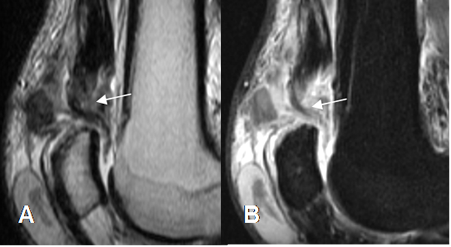

Fig 64 A. Ruptura parcial del cuadriceps.

A: RM sagital en T1 y B: RM sagital en STIR. Cambios inflamatorios en la inserción del tendón del cuadriceps, con discontinuidad de algunas fibras en la parte posterior, por ruptura parcial.